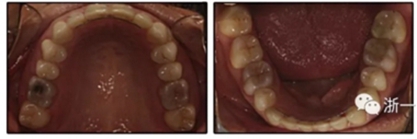

患者是一名39歲的白人婦女,病史不明。她主訴是她的右側(cè)顳下關(guān)節(jié)有不適癥狀,并希望改善她的笑容。她有一個(gè)對(duì)稱的臉型和一個(gè)II類2分類的微笑。她的側(cè)貌是凸的,90°的鼻唇角和骨性下頜骨發(fā)育不足??趦?nèi),上頜中線與面部重合,但下頜中線向右側(cè)偏移5mm;存在6mm的深覆蓋。她的兩側(cè)都是I類磨牙關(guān)系,左側(cè)是I類尖牙關(guān)系,右側(cè)是完全的II類尖牙關(guān)系。下頜右側(cè)第二前磨牙先天性缺失(圖1和圖2)。最初的全景片顯示了足夠的骨質(zhì)水平和全部的第三磨牙(圖3)。治療前的頭影測(cè)量片片和相應(yīng)的頭影測(cè)量圖(圖3)證實(shí)ANB為7°,Wits評(píng)估為6 mm的骨性II類錯(cuò)合(表)。上頜切牙相對(duì)與面部和顱底的位置很好。下頜切牙前傾。診斷為II類2分類錯(cuò)合畸形,伴有骨性下頜發(fā)育不足,右側(cè)顳下頜關(guān)節(jié)癥狀,下頜中線向右側(cè)偏移5mm,先天性右下第二前磨牙缺失。

患者決定采用非手術(shù)治療方法,側(cè)貌沒(méi)有任何預(yù)期的變化。治療后面部照片(圖5)顯示她改善的微笑和側(cè)貌,包括尖牙保護(hù)合。由于先天性第一前磨牙缺失,右磨牙關(guān)系為III類。治療后牙齒石膏模型(圖6)顯示實(shí)體牙齒交錯(cuò)排列情況,并且全景X線片顯示可接受的牙根平行度而且沒(méi)有牙根吸收表現(xiàn)(圖7)。最終的頭影測(cè)量片(圖7)證實(shí)了面部評(píng)估,并且描跡圖顯示深覆蓋的改善,同時(shí)保持上頜切牙位置并通過(guò)測(cè)量ANB角度和Wits評(píng)估改善骨性II級(jí)關(guān)系(表)。治療前后的疊加圖顯示由于下頜切牙前傾的增加改善了下唇平衡(圖8)。如相關(guān)治療計(jì)劃所預(yù)測(cè)的那樣,B點(diǎn)出現(xiàn)。A進(jìn)行牙科錐形束計(jì)算機(jī)斷層掃描以記錄下頜前牙區(qū)的骨質(zhì)變化。如預(yù)期的那樣,由于治療導(dǎo)致該區(qū)域的骨量增加(圖9)。

最終評(píng)估結(jié)果如下:(1)美觀改善; (2)達(dá)到了生理功能; (3)患者對(duì)治療結(jié)果完全滿意; (4)上頜尖牙的角度和下頜切牙的傾斜度有所改善(表); (5)形成了穩(wěn)定的牙周終點(diǎn),并觀察到附著齦的厚度改善; (6)病人會(huì)從下頜前移中受益,但她不想改變她的側(cè)貌; (7)長(zhǎng)期變化(6年)是穩(wěn)定的,在B點(diǎn)再生的骨保持穩(wěn)定,咬合關(guān)系得到改善(圖10和11;表)。